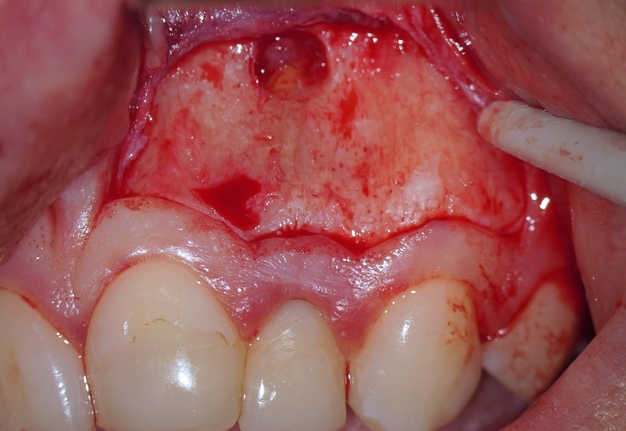

Once the apical microsurgery has been completed great care has to be taken in repositioning and suturing the elevated soft tissue. In fact, the ultimate esthetic result of the soft tissue manipulation depends on several factors such as the type of tissue, the type of incision, the choice of instruments used to incise, elevate, and retract the flap as well as careful reapproximation and a proper suture technique.

It is recommended to moisten the soft tissue with a wet gauze (sterile water or saline) before it is repositioned. The soft tissue can become dehydrated during the procedure and rehydrating it will return its natural elasticity and allows for easier reapproximation [17]. When flap shrinkage persists despite tissue rehydration, a supplementary horizontal incision may be performed at the flap base to generate a variable-thickness flap, thereby enhancing tissue adaptability and reducing contractile tension.

A good recommendation is compression of the repositioned flap with a saline-moistened piece of gauze is necessary to create a thin fibrin layer between flapped tissue and cortical bone [16].